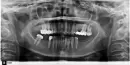

Какие зубы необходимо предварительно лечить? Какие коронки подойдут на передние зубы? Какие коронки подойдут на жевательные зубы? Цвет коронок из шкалы? Возможно установить мосты сверху (справа и снизу) слева? Сколько имплантов необходимо установить с правой стороны? Достаточно для имплантатов костной ткани?

Прикрепленые фото

С полной точностью по фото составить план лечения, безусловно, невозможно. Необходим очный клинический осмотр полости рта.

1. есть вопросы по лечению 14-го, 12-го, 11-го, 21-го зуба и оценить состояние 34-го зуба;

2. стоит оценить окклюзионные контакты, возможно, допустимо будет установить виниры;

3. жевательную группу зубов с правой стороны на верхней челюсти можно восстановить одиночными коронками, слева мостовидный протез, на нижней челюсти слева можно рассмотреть имплантацию, слева в идеале тоже имплантация;

4. цвет определяется непосредственно в кресле при естественном освещении, по фото подбор сомнителен и ошибочен с вероятностью 100 процентов;

5. на верхней челюсти мост во втором сегменте, то есть слева возможен, а вот на нижней челюсти может оказаться недостаточно прочным, ввиду отсутствия моляра;

6. на нижней челюсти слева в третьем сегменте в идеале необходимо установить 2 импланта, но результат зависит от КЛКТ и возможностей материальных, в том числе. Это определяется по трехмерному снимку.